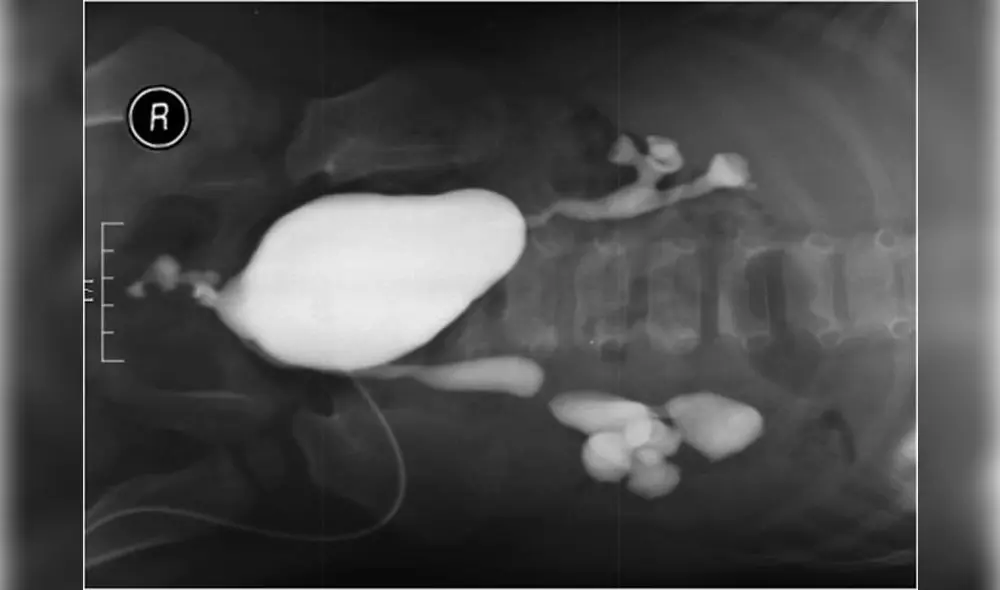

El equipo especializado de médicos y cirujanos de Turquía recibió el caso a un día del parto. Entonces descubrieron que, además de agenesia del pene, el pequeño presenta reflujo vesicoureteral y fístula vesicorectal.

Es decir, su orina retrocede de manera anormal desde la vejiga por los uréteres ante la presencia de un canal anormal entre la vejiga y el recto. Un caso enigmático.